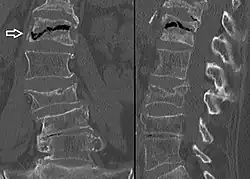

A compression fracture is a collapse of a vertebra. It may be due to trauma or due to a weakening of the vertebra (compare with burst fracture). This weakening is seen in patients with osteoporosis or osteogenesis imperfecta, lytic lesions from metastatic or primary tumors,[1] or infection.[2] In healthy patients, it is most often seen in individuals suffering extreme vertical shocks, such as ejecting from an ejection seat. Seen in lateral views in plain x-ray films, compression fractures of the spine characteristically appear as wedge deformities, with greater loss of height anteriorly than posteriorly and intact pedicles in the anteroposterior view.[3]

Compression fractures are usually diagnosed on spinal radiographs, where a wedge-shaped vertebra may be visible or there may be loss of height of the vertebra. In addition, bone density measurement may be performed to evaluate for osteoporosis. When a tumor is suspected as the underlying cause, or the fracture was caused by severe trauma, CT or MRI scans may be performed.

Compression fracture of the fourth lumbar vertebra post falling from a height. -